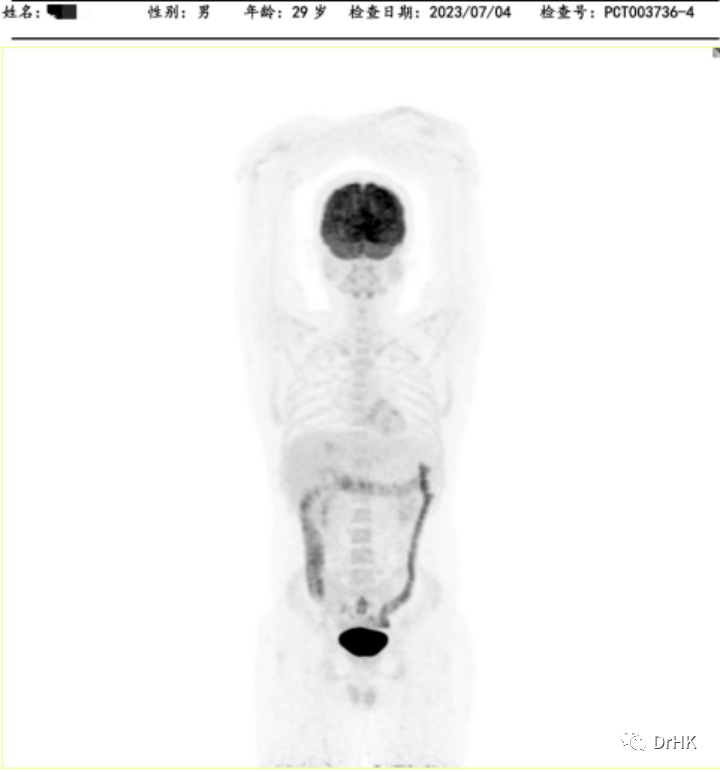

Starting from April 2, 2022, the patient was treated with the DA-TEDDi-R regimen combined with targeted therapy (ibrutinib + rituximab + dexamethasone + liposomal doxorubicin + etoposide + temozolomide + long-acting GCS + intrathecal Ara-C) for two cycles. After the treatment, the PET-CT assessment showed complete metabolic remission (the first complete remission since the onset of the disease), with a Deauville score of 2-3. Comparing this with the PET/CT imaging from our center on April 1, 2022, the liver lesion significantly decreased and the high metabolic activity disappeared; the left gluteus maximus lesion also disappeared. There were localized bone resorption and destructive changes in multiple bones (bilateral scapulae, clavicles, ribs, sternum, pelvic bones, and vertebrae), with some areas showing increased bone density, particularly in the left iliac bone. The bone marrow glucose metabolism was diffusely elevated, suggesting reactive changes post-treatment, and we recommended further evaluation with a bone marrow biopsy.

The patient was subsequently followed up regularly, with imaging evaluations completed six months and one year after the transplant. It is gratifying to report that the patient has maintained complete remission throughout this period. The PET images are shown below:

One-Year Post-Transplant Imaging Evaluation